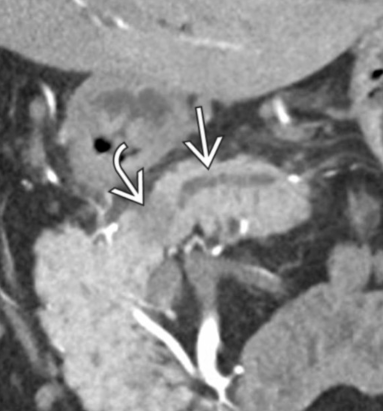

- Infiltration artérielle: <180° vs >180° et cranio-caudalement >2cm vs <2cm

- Infiltration veineuse: Contact, engainement, sténose, occlusion

- Infiltration de la lame rétroporte (entre l’AMS et l’uncus)